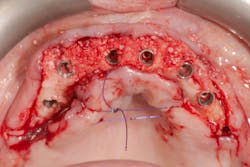

Placement of narrow implants. In a full-arch restoration in the presence of alveolae and thin ridges, narrow implants allow the placement of more biomaterial in the alveolae for ridge preservation. Bone grafting will be avoided in the presence of the ridges.